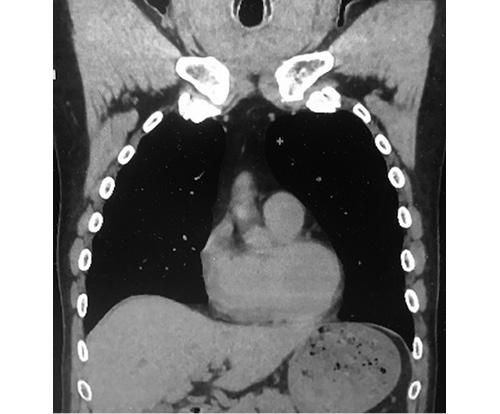

2. Fig. 2. MSCT of the chest in a longitudinal section. | |

| Subject | ||

| Type | Other | |

View

(46KB)

|

Indexing metadata ▾ | |